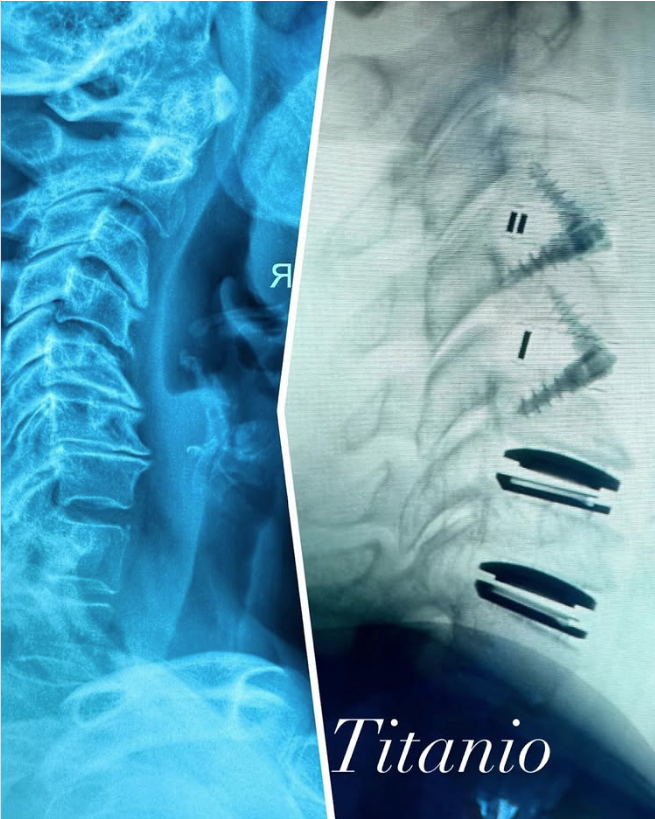

Muestra Alejandra Guzmán la radiografía de su columna tras delicada cirugía

A través de sus redes sociales, la intérprete de Eternamente bella, compartió con sus fans la posible colocación de piezas de titanio o prótesis

Alejandra Guzmán fue sometida a una delicada operación de columna vertebral el 7 de octubre de 2025. De acuerdo con información de Infobae, la radiografía que la artista compartió en su cuenta oficial de Instagram muestra la posible colocación de piezas de titanio o una prótesis, elementos visibles en la imagen difundida.

La intérprete de Reina de corazones acompañó la publicación con un breve mensaje que llamó la atención de sus seguidores: “Abrazo biomecánico”.

“Esta es la mejor etapa de mi sanación. Este es el fin de tanto, tanto que he pasado en estos trece años”. La cantante acompañó su mensaje con imágenes comparativas de resonancias magnéticas que mostraban el antes y después de la operación. En ellas aseguró sentirse “increíble” y “bien operada”.